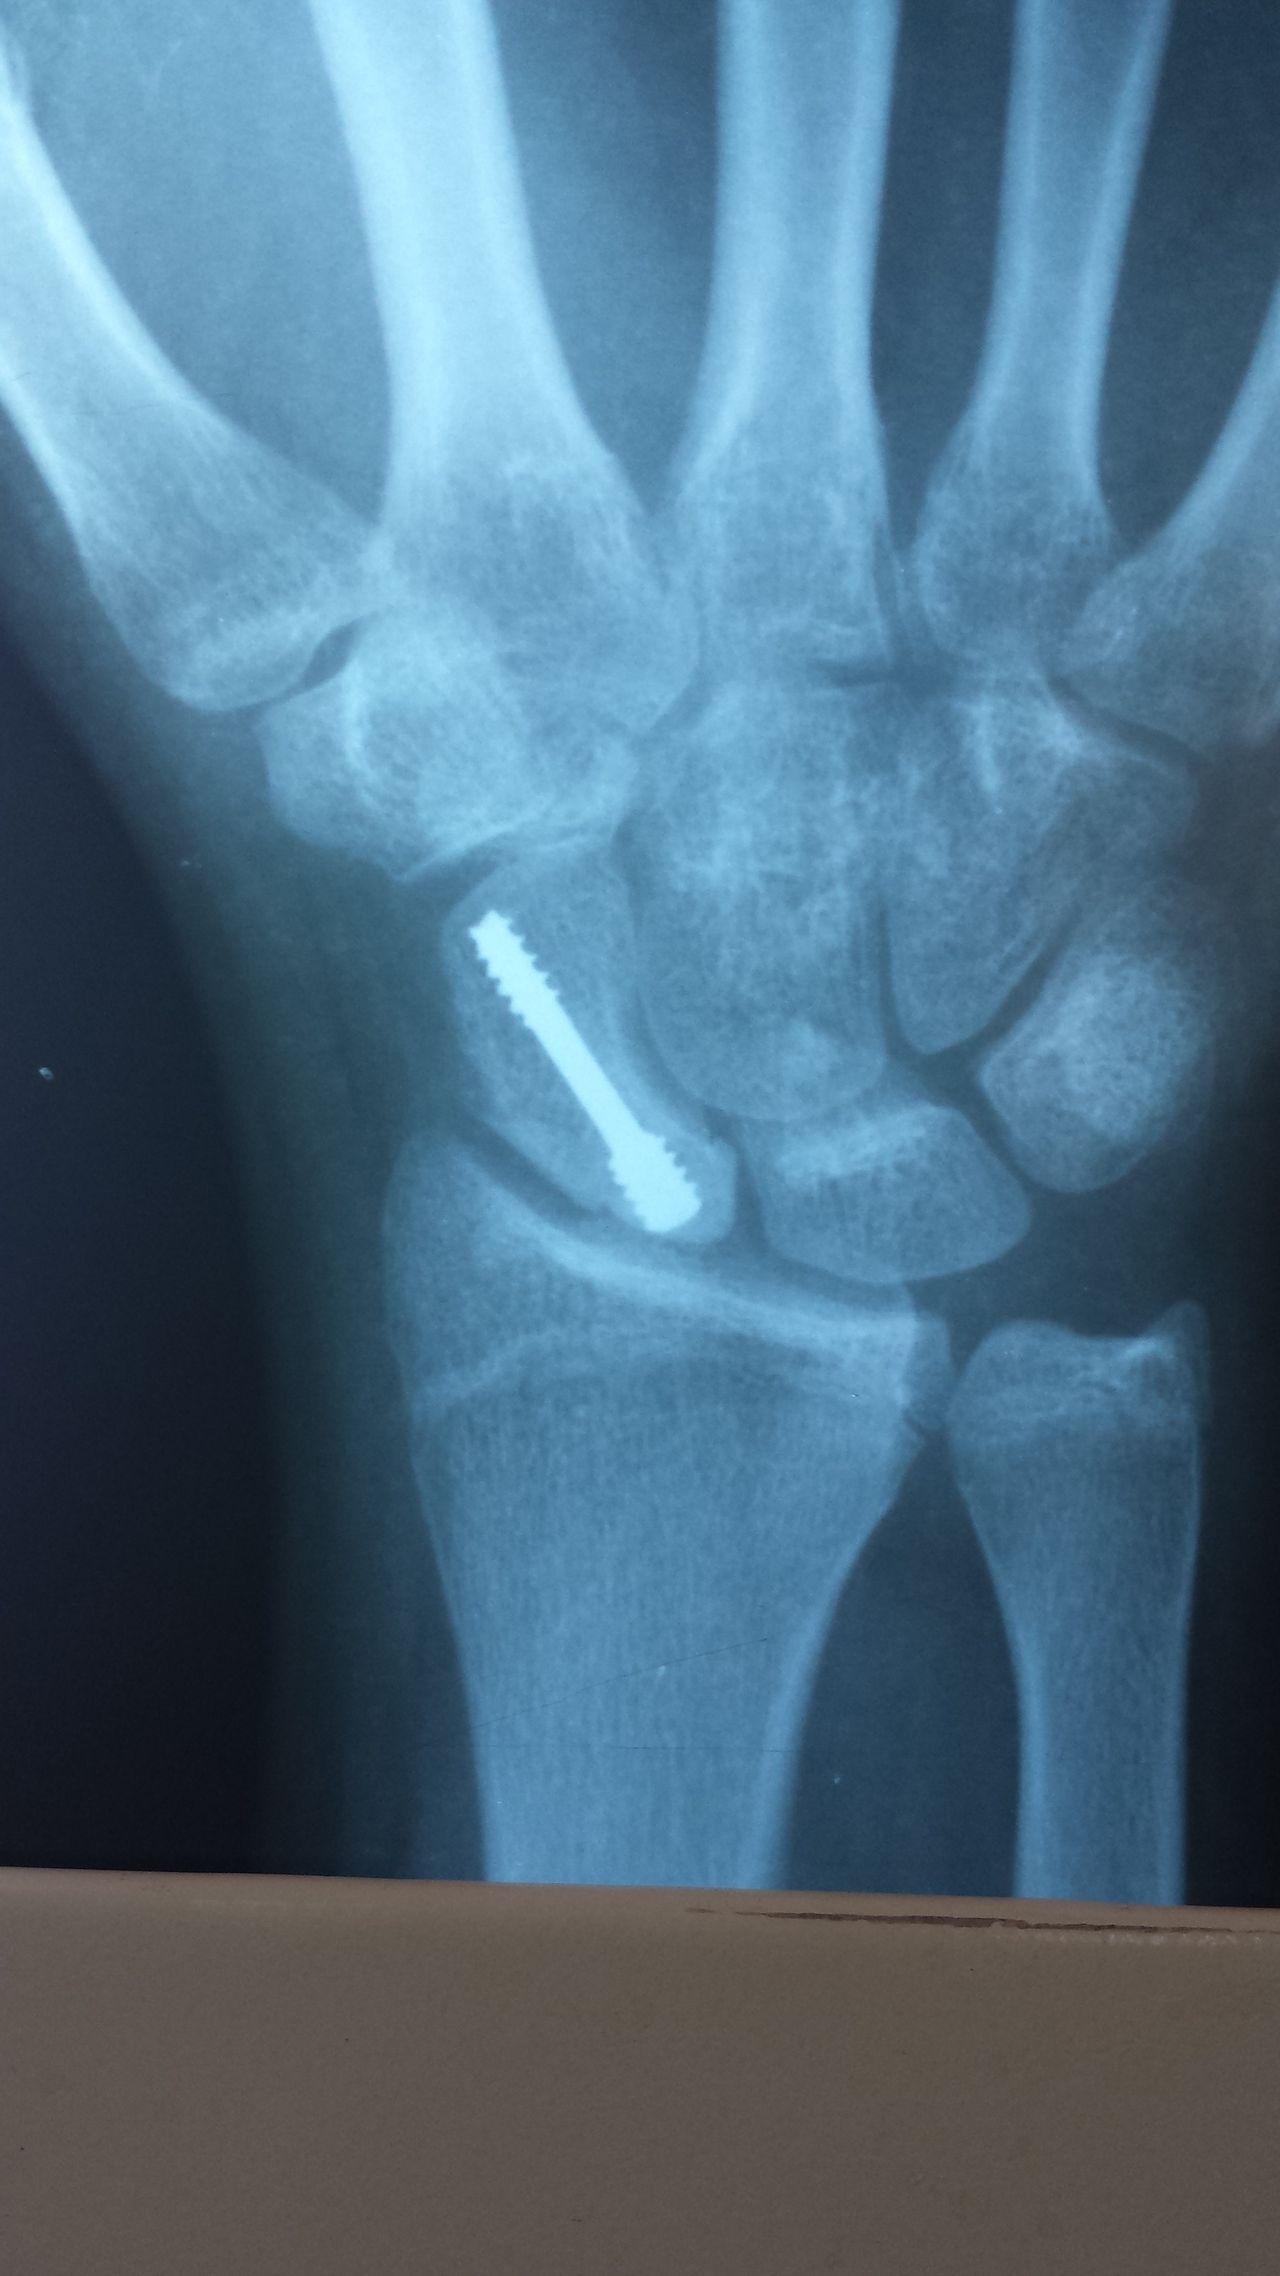

-ESCAFÓIDE: Tratamento da Fratura e da Pseudo-artrose do Escafóide com ou sem DISI e outras complicações, bem como Lesões Ligamentares da Mão e Punho, incluindo as do Ligamento Escafo-lunar do Carpo. Bennett, Rolando, Barton, Monteggia, Galleazzi e outras fraturas especiais ou comuns.

-FRATURAS: do antebraço, punho, metacarpos e  falanges.

• Redução Cirúrgica Da Fratura De Osso Do Carpo

• Tratamento cirúrgico da pseudoartrose da ossos carpiano